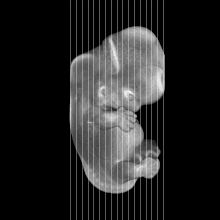

MRI Slice Selector

Mouse: click on a line below to select a view

Finger: tap a line below with a very light touch